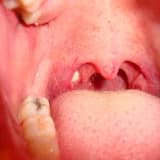

Bademcikler düzensiz yüzeyli pürüzlü organlardır. Üzerlerinde çok sayıda Crypts adında çukurlar ve boşluklar bulunur. Dökülen mukoza hücreleri, yemek parçaları ve bademcik iltihabi kalıntıları tükürükle yutulurken bazı kişilerde bademciklerdeki çukurlarda birikir ve mikropların yaşamı için uygun ortam sağlar ve ‘’Kronik Tonsillit’’ , ‘’Tonsillolith’’ gibi bademcik hastalıklarına yol açar. Bu birikintileri Hydrovacuumaspiration’’ (HVA) yöntemiyle temizleyerek ve bağışıklık sistemine destekleyici tedavi vererek tekrarlayan bademcik iltihapları önlenebilmektedir. Ayrıca HVA tekniğiyle bademcik yıkaması ağız kokusuna (Halitozis) sebep olan bademcik taşlarının (Tonsillolith) giderilmesinde de son derece etkili ve güvenli bir yöntem olarak kendini kanıtlamıştır.

Bu yöntem özel tasarlanmış cihaz ile negatif basınç uygulanarak bademcikteki patolojik birikintilerin çekilmesinden ve aynı anda antibiyotikli solüsyonlarla basınçlı yıkamadan oluşmaktadır. Yıkama işlemi esnasında öğürme refleksi olacağından hasta aç olmalıdır. Hastaya işlem öncesi detaylı bilgi verilir ve onamı alınır. Hasta KBB sandalyesine oturtulur ve eğer lokal anestetik (uyuşturucu) ilaçlara alerjisi yoksa boğazına ilaç sıkılarak uyuşturulur. Hastanın eline istediğinde tükürebilmesi için böbrek küvet verilir. İşlem esnasında hastanın uyumu çok önemlidir ve tedavi başarısıyla doğrudan ilişkilidir. Doktor gerekli ekipmanı hazırladıktan sonra hasta ağzını geniş açar ve derin nefes alıp 5 saniye nefesini tutmaya çalışır. Hekim özel tasarlanmış cihazın gevşetme düğmesini basılı tutarak bademciğe yerleştirir ve düğmeyi bırakır. 1, 2, 3, 4, 5 diye sesli sayar ve gevşetme düğmesine basarak bademcikten ayırır. Bu esnada hastanın ani hareketlerden kaçınması çok önemlidir. durulmasını istediği anda hasta müsait elini kaldırarak işaret eder ve hekim hemen aleti hastanın bademciğinden ayıracaktır. Aynı şekilde bademciğin diğer kısımlarına ve ikinci taraf bademciğe 3-4 defadan uygulanır.